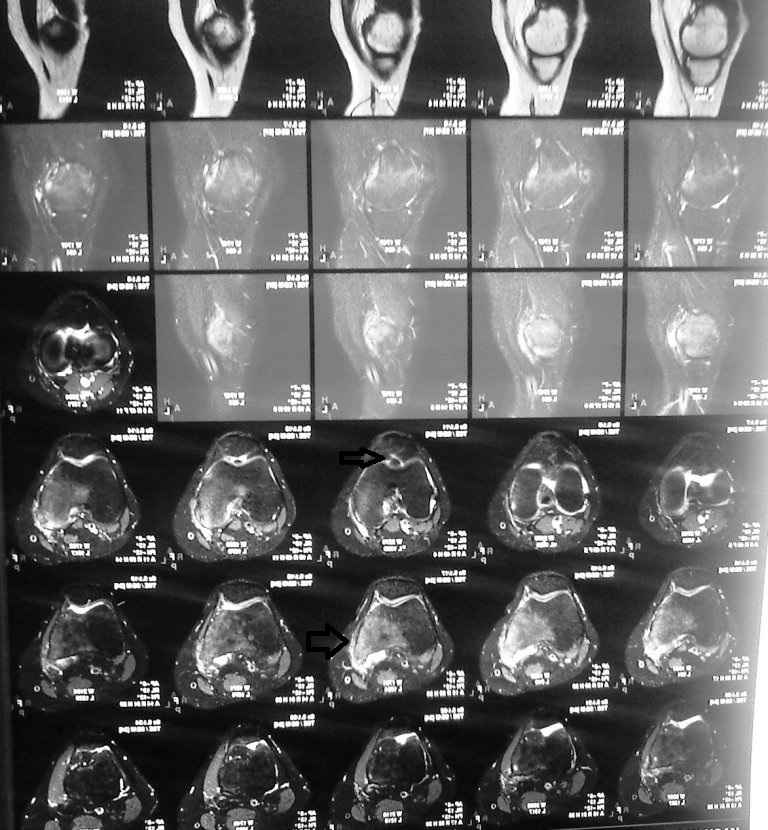

Пациентку беспокоит правый тазобедренный сустав в области вертела (именно там где имеются рентгенологические проявления . Сегодня мне были доставлены выполненное ей ранее РКТ правого коленного сустава(имеются выраженные изменения (лизис мыщелка бедра и дополнительное образование в межмыщелковом возвышении) . В биохимических анализах по ревматоидной программе изменений нет. В ОАК повышена СОЭ (29).

а мне кажется что есть изменения в большом трохантере правого бедра , смешанного характера(лизис склероз) стерты границы латерального кортекса и мягкие ткани не так четко видны как справа .. МРТ , костное сканирование , если что то есть - костная биопсия с бактериологическим исследованием ...

Именно изменения в большом вертеле меня и интересуют. К сожалению результаты костной биопсии у нас в учреждении в связи с особенностью изготовления костного препарата нужно ожидать более 10 дней. консультирована пациентка и фтизиоостеологом-убедительных данных за свою патологию он не видит.

процесс хронический так что 10 дней не срок , к тому же микобактерии выращивают до полутора мес .

идите на биопсию но сначала МРТ + сканирование .

В верхней части диафиза выраженная периостальная реакция, над черной полосой закрывающей имя пациентки. Наверное туберкулез. Нужна биопсия и посев.

Уважаемый Олег! У больной, вероятней всего, имеется туберкулезный трохантерит справа (незначительные боли, ограничение функции тазобедренного сустава, на Р-грамме - остеопороз!!!, деструкция б.вертела, уплотнение мягких тканей. Больной показана операция - некрэктомия очага деструкции и пластика аутокостью. Бак. и гистологическое исследование операционного материала верифицирует патологический процесс. Кстати, замечу ответственно уважаемому ортопедическому сообществу, положительные результаты посева на микобактерию туберкулеза при активных процессах составляют всего 20-25%, так что отрицательный посев не означает исключение туберкулезного процесса! Желаю успехов!